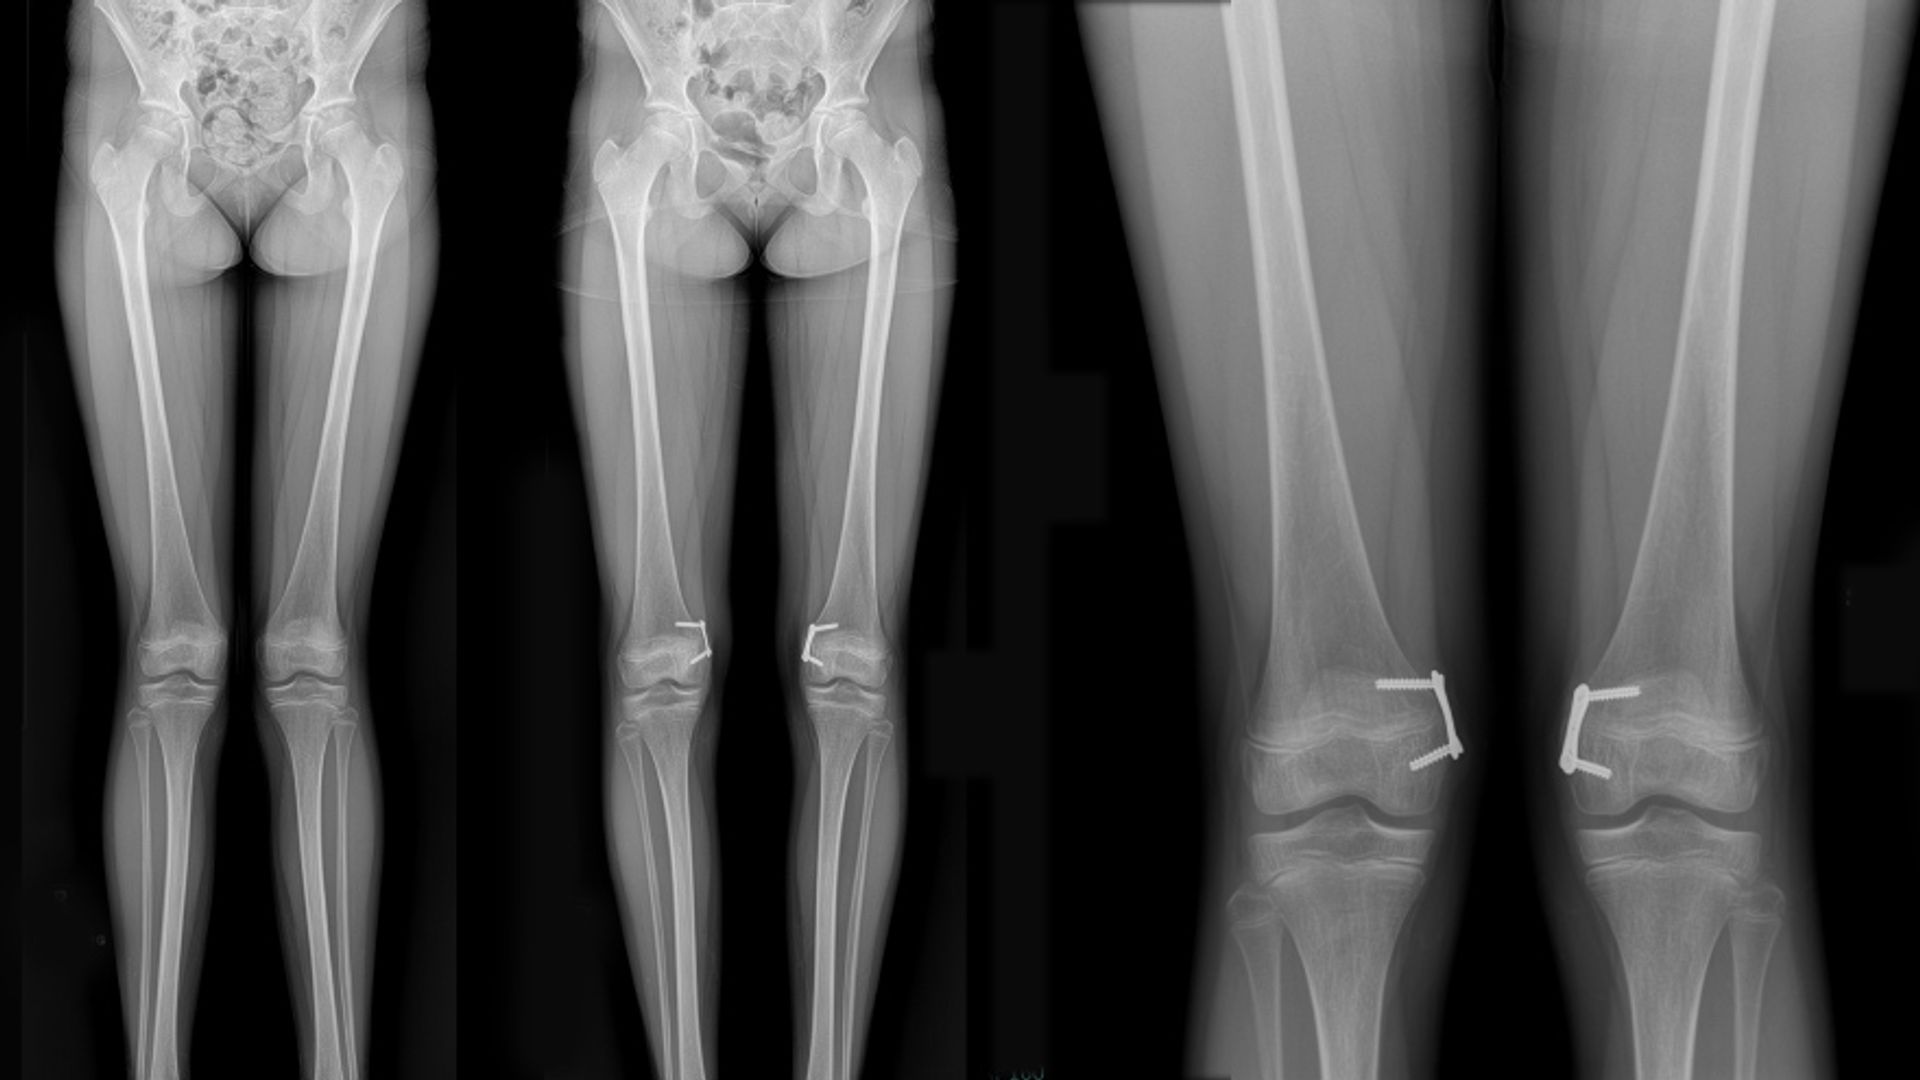

Genu valgum (knock-knees) is a common lower leg abnormality usually seen in toddlers, preschool, and early school-age children. Images left to right: Patient presenting with genu valgum, post-genu valgum with posts in place, and detail of post positioning.